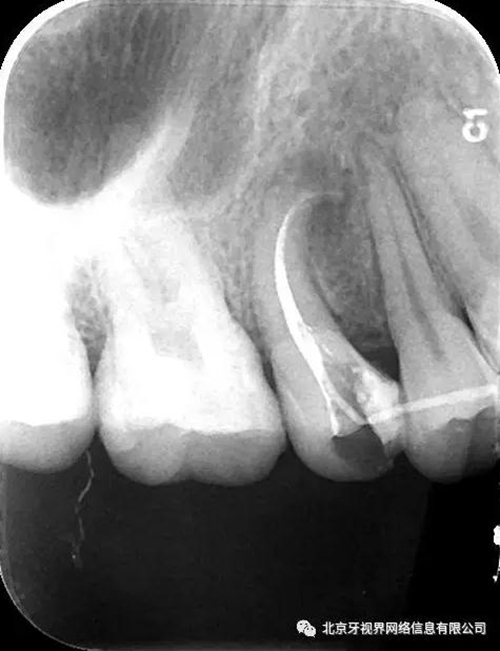

15備洞,揭頂,10#擴(kuò)大器預(yù)彎后疏通至全長,次氯酸鈉加超聲蕩洗,氫氧化鈣糊劑封藥,玻璃離子暫封,隨診。

4.此例病例中,術(shù)前分析后,采取先解放其中上段后,10#擴(kuò)大器預(yù)彎緩慢前行,抵達(dá)根尖區(qū)。